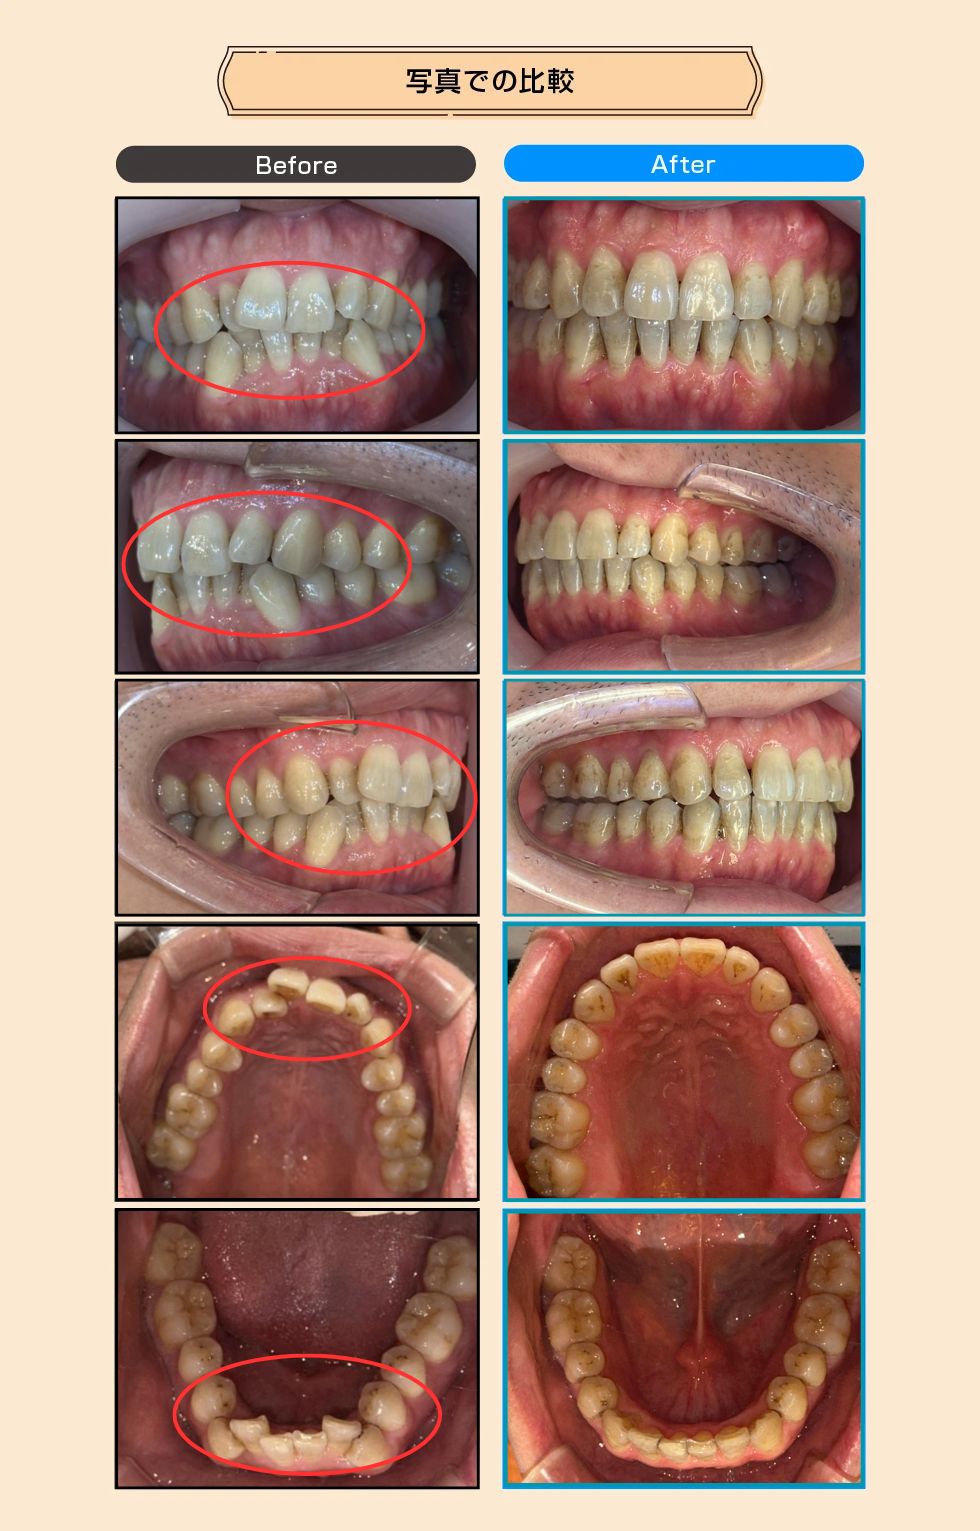

【症例No.1287】 上下のデコボコ(叢生)

上下のデコボコ(叢生)

前歯の歯並びをキレイにしたいとのことでご相談いただきました。マウスピース型矯正装置を用い、抜歯を行わずに歯列を整える計画を立てました。歯並びの改善だけでなく、口元を閉じた時のスッキリ感が出るよう調整し、お顔全体の印象も若々しく(アンチエイジング)変化しています。

| 治療内容 | マウスピース型矯正装置を用いた矯正治療。抜歯は行わず、IPR(歯と歯の間のエナメル質をわずかに削る処置)を11カ所施すことで、歯を並べるためのスペースを確保しました。 |

| ドクターから一言 | 抜歯をせずにIPR(11カ所)を適切に行うことで、健康な歯を残したまま美しい歯列を実現しました。口元のシルエットもスッキリと改善されています。 |